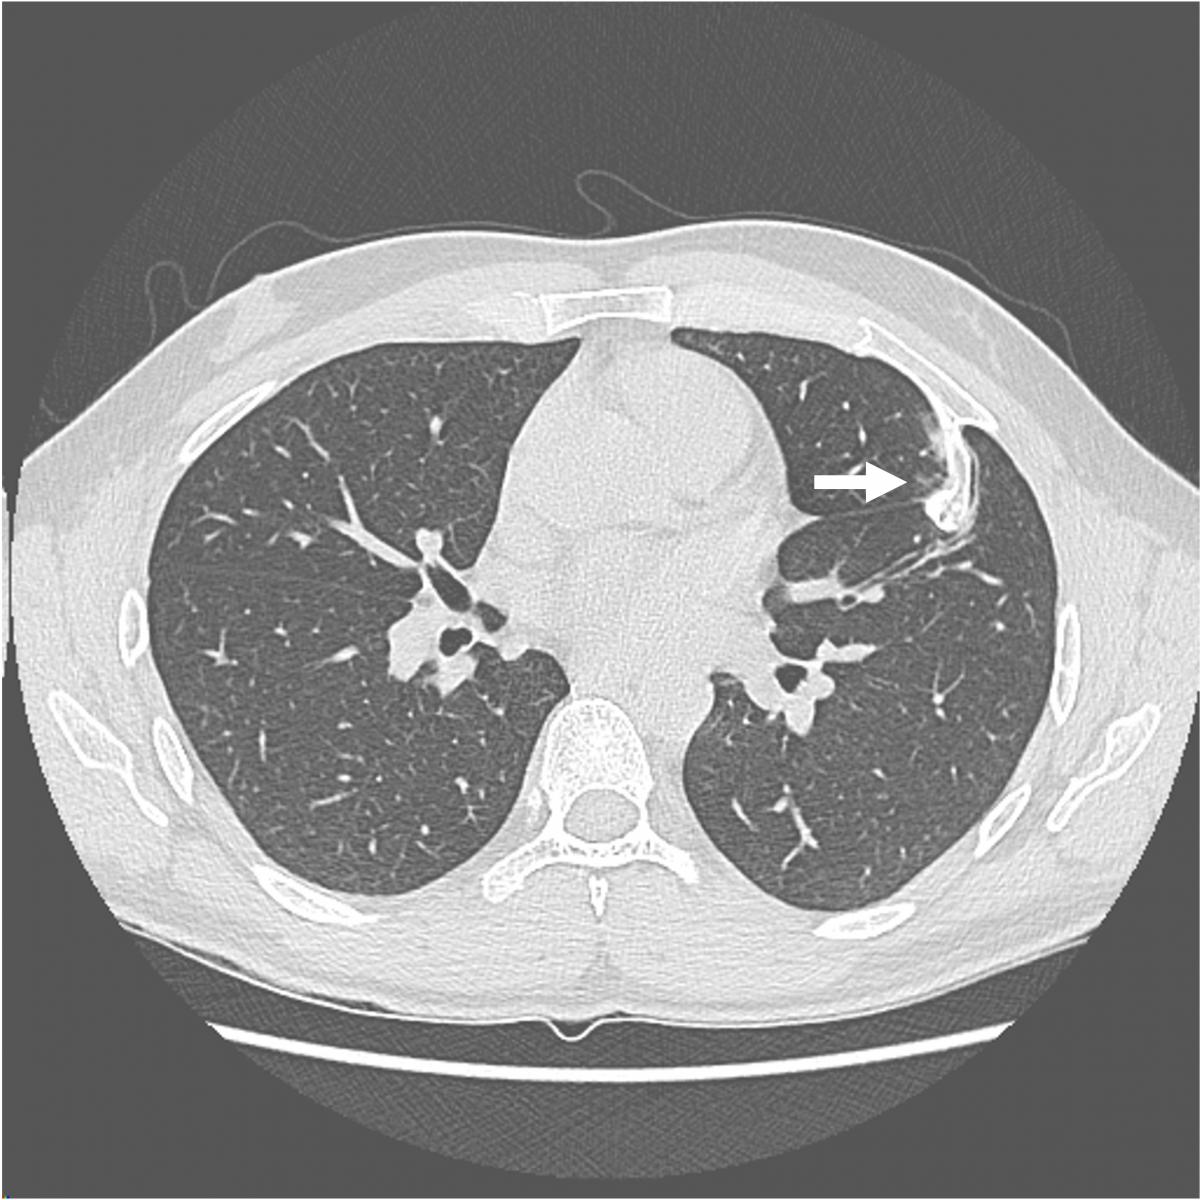

This video shows the case of a forty-year-old man who presented for evaluation of several months of anterior chest wall pain. Cross sectional imaging demonstrated a calcified anterior fourth rib lesion arising from the posterior table and projecting inward into the left hemithorax, measuring up to 3.8 cm (Figure 1).

Surgeons elected to begin the operation by performing a thoracoscopic evaluation to localize the lesion and evaluate for any pleural adhesions. The patient was placed in a semi-right lateral decubitus position. An incision was made at the seventh intercostal space at the anterior axillary line and a thoracoscope was introduced. Inspection of the pleural space demonstrated a bony spur arising from the fourth rib (Figure 2).